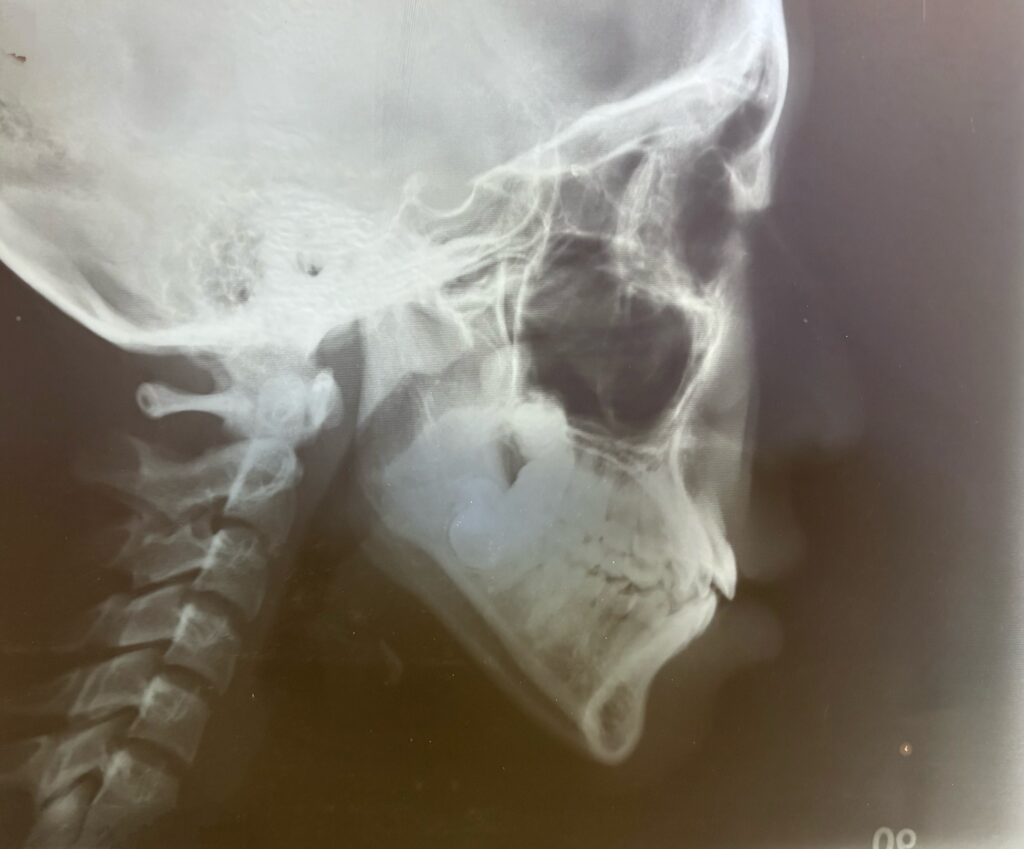

まず①骨格(森)の診断に用いるのが、「セファロ写真」と呼ばれる横から撮影した頭部X線規格写真です。

このセファロ写真をもとに、顎全体のバランスや、横顔のEラインを含めた軟組織の状態を分析します。

実際のセファロ写真とあわせて、私がトレース(分析用の線を引く作業)を行った資料もご覧いただいています。

一人ひとりのセファロを丁寧に計測し、数値として確認することで、

感覚だけに頼らない、より正確な診断を行っています。